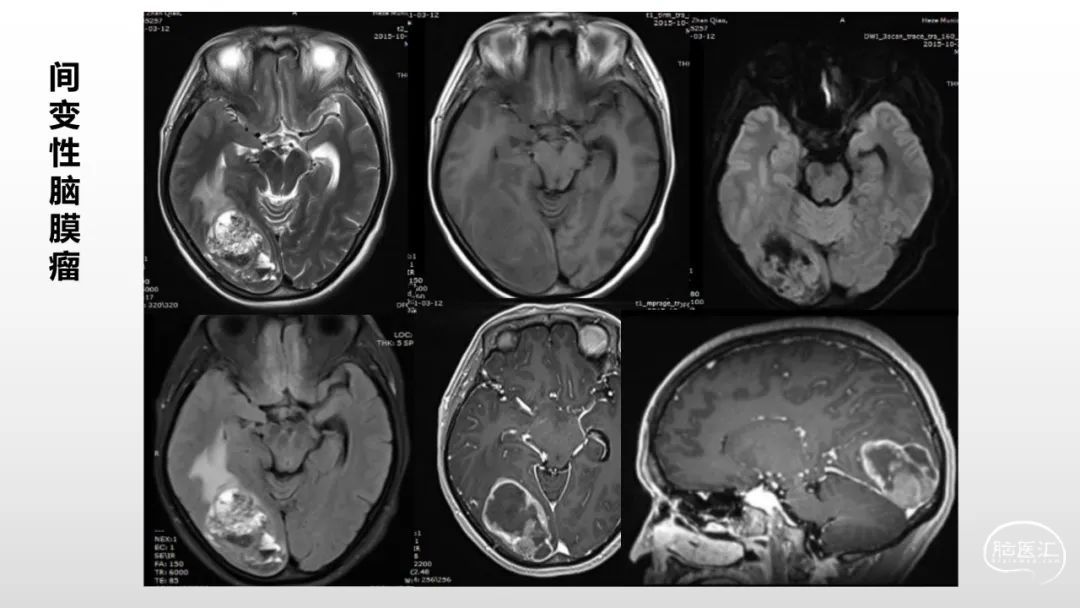

颅脑影像诊断基础知识讲座:脑膜病变